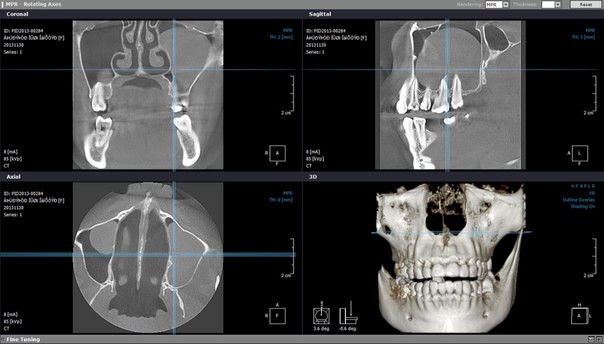

КОМПЬЮТЕРНАЯ ТОМОГРАФИЯ ПРИДАТОЧНЫХ ПАЗУХ НОСА

В ЖЕЛЕЗНОДОРОЖНОМ

К сожалению, очень часто бывают ситуации, когда люди запускают инфекционные болезни, в результате чего придаточные пазухи носа воспаляются, возникают серьёзные проблемы со здоровьем, и человеку ставят диагноз "синусит". Однако, прежде чем доктор определится с заключением, он отправляет больного на рентгенографию или компьютерную томографию, дабы удостовериться в своих подозрениях. Об одном из этих методов исследования сегодня и пойдёт речь.

В зависимости от того, какое конкретно у больного обнаружено воспаление, назначается лечение придаточных пазух носа. Но для того чтобы поставить точный диагноз, врач вначале направляет пациента на определённые исследования. Зачастую специалист назначает рентгенографию, но в отдельных случаях может дать направление на компьютерную томографию. Более детально об этом способе исследований пазух носа пойдёт речь ниже.

В каких ситуациях проводится КТ? Это исследование в некоторых случаях необходимо проводить, чтобы исключить опасные заболевания такого важного органа, как нос.

Придаточные пазухи носа проверяются с помощью томографа в таких ситуациях:

Плюсы компьютерной томографии Этот метод считается одним из самых точных при обследовании такого органа, как нос.

Придаточные пазухи носа проверяются досконально, что говорит о высоком качестве и безошибочности анализа. Этот метод диагностики имеет такие преимущества: